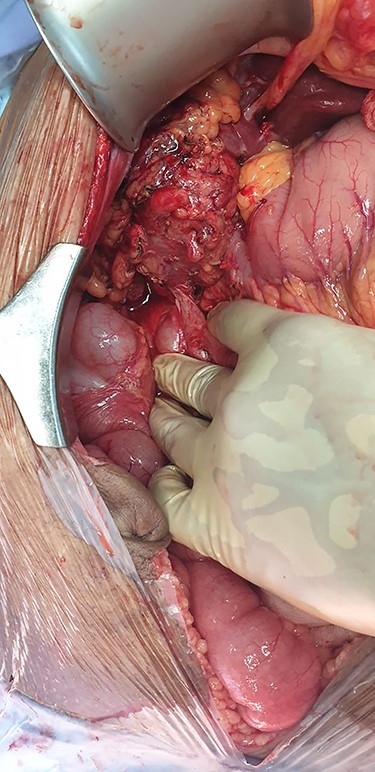

The patient was sent for a laparotomy during which a thickened gallbladder with significant adhesions was noted. A cholecystocolonic fistula was seen involving the proximal transverse colon (Fig. 6). Following adhesiolysis, a cholecystectomy was performed followed by a segmental resection of the colon and fistula with a primary anastomosis of the bowel. The catheter was flushed, and a drain placed into the gallbladder bed. The drain was removed after 4 days, and he was subsequently discharged after recovery.

Intra-operative imaging obtained via laparotomy of the abdomen, demonstrating a fistulous connection between the hepatic flexure of the colon and an inflamed, granulomatous gallbladder.